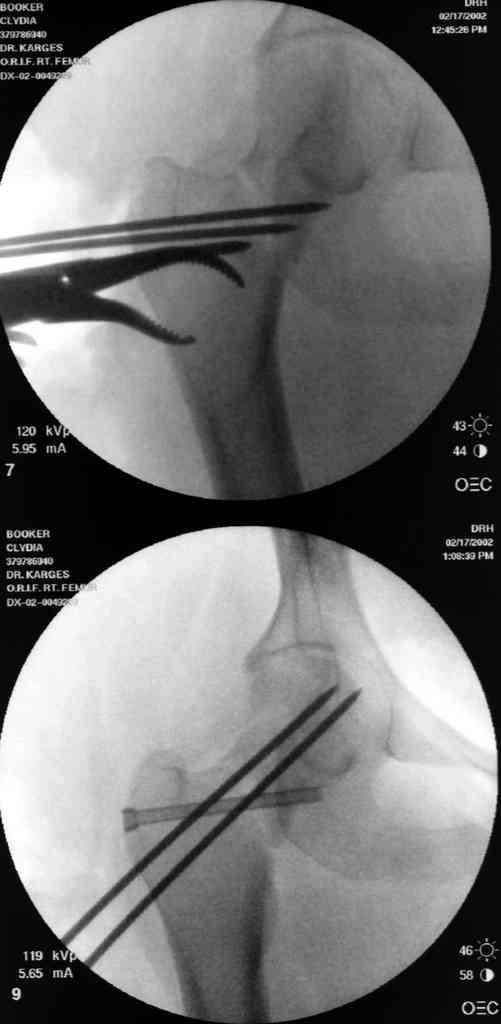

На снимках ложный сустав шейки бедра, несостоятельность фиксации. По положению шурупа можно предсказать ложный сустав, например, если screw backup за кортикальный слой около 15-20 мм, и также изменение угла от первоначального.

№2-3 типичная ошибка несоблюдения концепции параллельности шурупов, нарушение-фиксация поперечным допольнительным шурупом для приближения отломка в результате не сработало метод параллельных шурупов

№4 результат на КТ